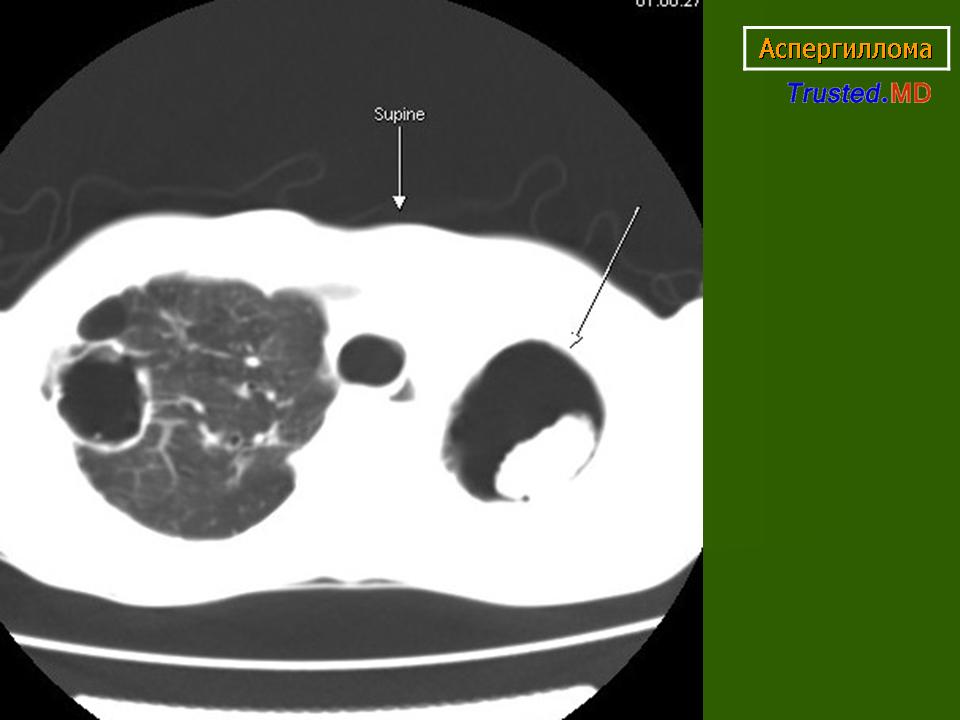

Аспергиллома

Приложения:

1.asp_.slayd6_.jpg2.asp_.slayd7_.jpg3.asp_.slayd8_.jpg